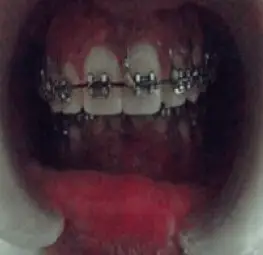

A 20 YEAR OLD FEMALE PATIENT REPORTED TO SGT DENTAL COLLEGE WITH THE CHIEF COMPLAINT OF BACKWARDLY PLACED LOWER JAW AND WANTED CORRECTION FOR THE SAME. SHE WAS DIAGNOSED WITH RETROGNATHIC MANDIBLE CLASS II. AFTER THE PREOPERATIVE ORTHODONTIC PHASE IN THE DEPARTMENT OF ORTHODONTICS , THE PATIENT WAS REFERRED FOR THE SURGICAL PHASE TO THE DEPARTMENT OF ORAL AND MAXILLOFACIAL SURGERY.

PRE-OPERATIVE PICTURES

RETROGNATHIC MANDIBLE

BILATERAL SAGITTAL SPLIT OSTEOTOMY (BSSO) WITH 7MM ADVANCEMENT OF THE MANDIBLE ALONG WITH ADVANCEMENT GENIOPLASTY OF 4MM WAS DONE UNDER G.A.